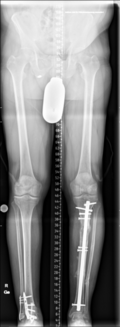

Oberschenkelamputation nach periprothetischer Tibiafraktur bei nicht sanierter periprothetischer Kniegelenksinfektion

Kurze Vorgeschichte: Herr S, ein 67-jähriger Patient, erhielt 2011 (Abbildung 1) bei ausgeprägter Gonarthrose eine primäre KTEP rechtsseitig. Im weiteren Verlauf zog er sich 2017 eine periprothetische Tibiafraktur zu, die mit einem Knieendoprothesenwechsel auf ein achsgeführtes Implantat (Abbildung 2) und Schaftverlängerung der Tibia im September 2017 ex domo therapiert wurde. Im Verlauf zeigten sich eine anhaltende Sekretion und eine partielle Nekrose am unteren Wundpol.

Im weiteren Verlauf zeigten sich die Weichteile des rechten Unterschenkels zunehmend mazeriert und belegt. Zudem sei der Patient erneut gestürzt. Eine erneut durchgeführte Röntgendiagnostik zeigte erneut eine periprothetische Tibiafraktur (Abbildung 3) bei einliegender achsgeführter KTP mit langem tibialem Stem und bekanntem periprothetischem Infekt mit Candida parapsilosis. Wir haben die Befunde ausführlich mit dem Patienten besprochen und in Zusammenschau der Befunde schließlich die Indikation zur Oberschenkelamputation gestellt.

Diese konnte komplikationslos im Mai 2018 durchgeführt werden (Abbildung 4 und 5).

Womöglich hätte der drastische Schritt einer Amputation durch eine frühzeitige Prothesensanierung, welche jedoch durch den Patienten abgelehnt wurde, verhindert werden können.